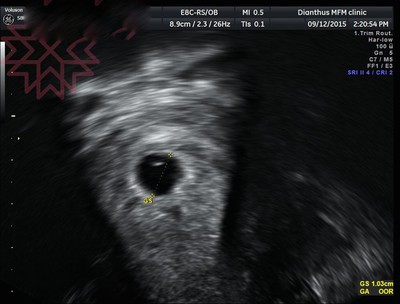

[6w]小寶的美妙心跳

小寶又挺進一關了,強而有力的規律心跳,證明我的身體不適來自有因~~~ 胚胎發育良好正常,大小也符合週期6w4d,真讓我們大大鬆了一口氣!!!! (小寶好棒!!!!!)圖下方的律動就是小寶的心跳哦,...